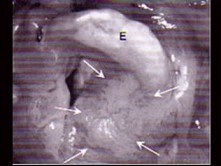

6.CT检查见下图,进一步的检查是  (    )